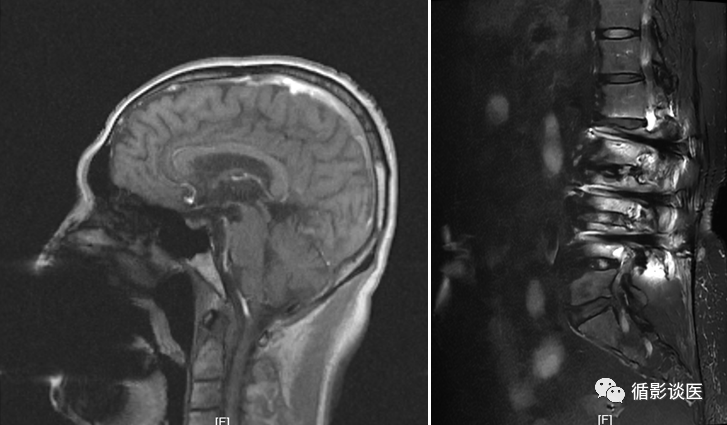

做核磁时遗忘或携带金属制品进行检查的图像和对机器造成影响。